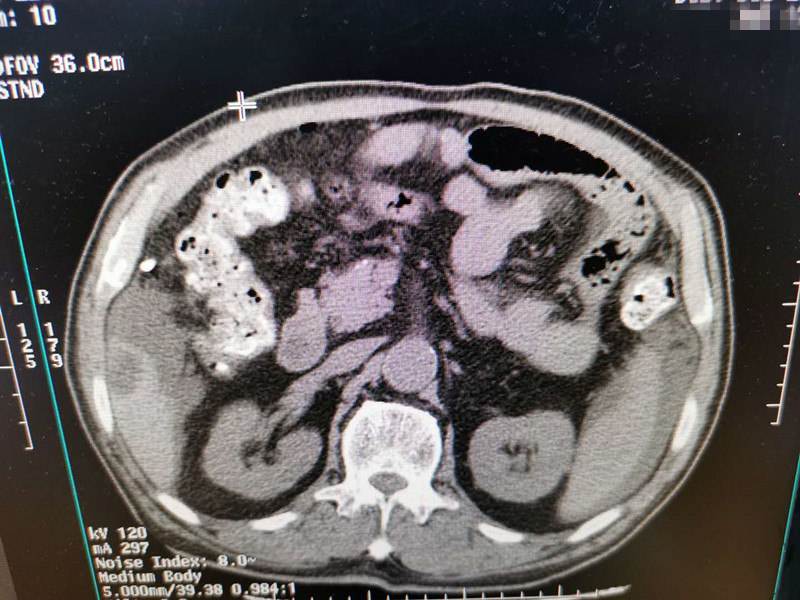

83岁肺部氩氦刀冷冻消融

发布人:美国氩氦刀技术官方网站    发布时间:2020/7/20 15:28:22